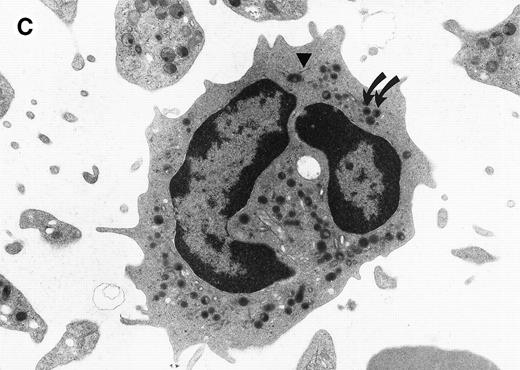

The morphological changes in the neutrophils of C/EBPε−/− mice suggest that C/EBPε transactivates target genes important in late myeloid differentiation.1Figure 1compares the ultrastructural morphology of peripheral blood granulocytes from C/EBPε−/− and wild-type mice. The EM study shows signs of cytoplasmic immaturity in C/EBPε−/− peripheral blood granulocytes. Rod-shaped tertiary granules are completely missing, the ratio of primary to secondary granules is increased, and the number of mitochondria/cell is higher in C/EBPε−/− granulocytic cells.

Electron micrograph of a peripheral blood neutrophil from a C/EBPɛ−/−mouse (A and B) and a wild-type mouse (C). (A) The C/EBPɛ−/− peripheral blood neutrophil shows signs of immaturity; the absolute number of granules is reduced and tertiary, bacilliform-shaped granules are missing. (B) Higher magnification of middle section of C/EBPɛ−/− neutrophil: The ratio of the larger, primary (electron-dense) granules (arrows) to the smaller less electron-dense, secondary granules is increased. In the less mature C/EBPɛ−/− neutrophils, most secondary granules appear electron-lucent, most likely due to extraction by glutaraldehyde fixation (arrowheads) as previously described.46 (C) For comparison, mature wild-type granulocyte has multiple, small secondary granules (arrows) and bacilliform tertiary granules (arrowhead).